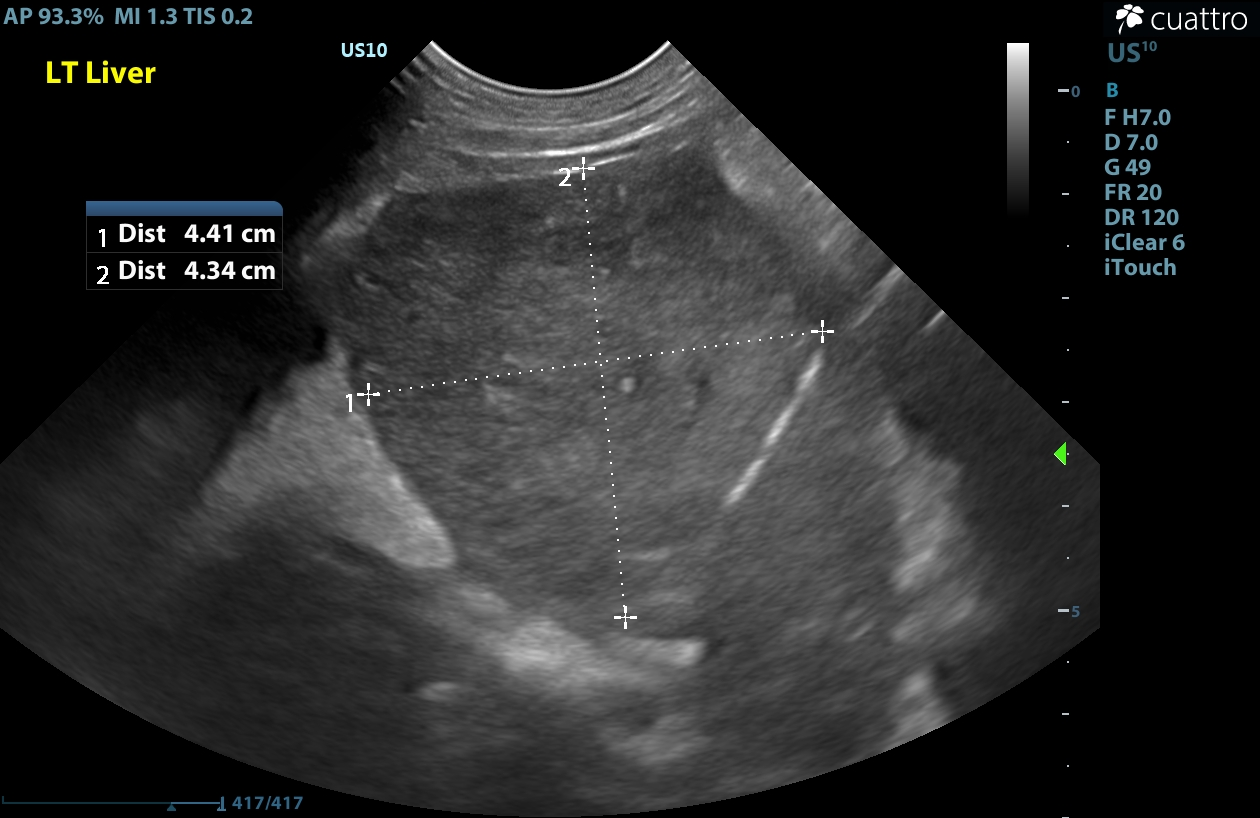

Liver: There is a contour deforming rounded mildly hypoechoic homogenous mass present in the medial left liver measuring 4.4x4.3cm-sagittal and 5.9x4.3cm-transverse. The tissue surrounding this mass is moderately-severely hyperechoic. The rest of the liver is normal size, shape and subjectively hypoechoic echogenicity.

Liver Mass - the findings are moderate - DDx: primary hepatic neoplasia vs. metastatic neoplasia vs. infiltrative neoplasia (lymphosarcoma) vs. benign nodules of regeneration.

Image 1: Rounded mildly hypoechoic mass on the left medial liver.